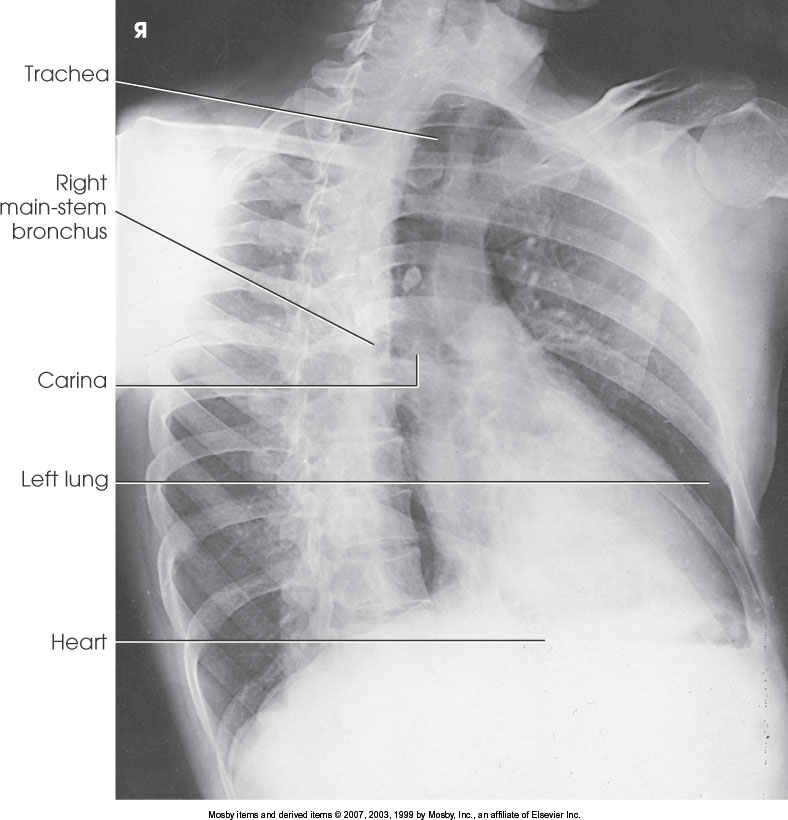

What position is demonstrated?

RAO Chest